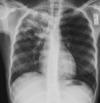

12

Q

A

Consolidación alveolar

How well did you know this?